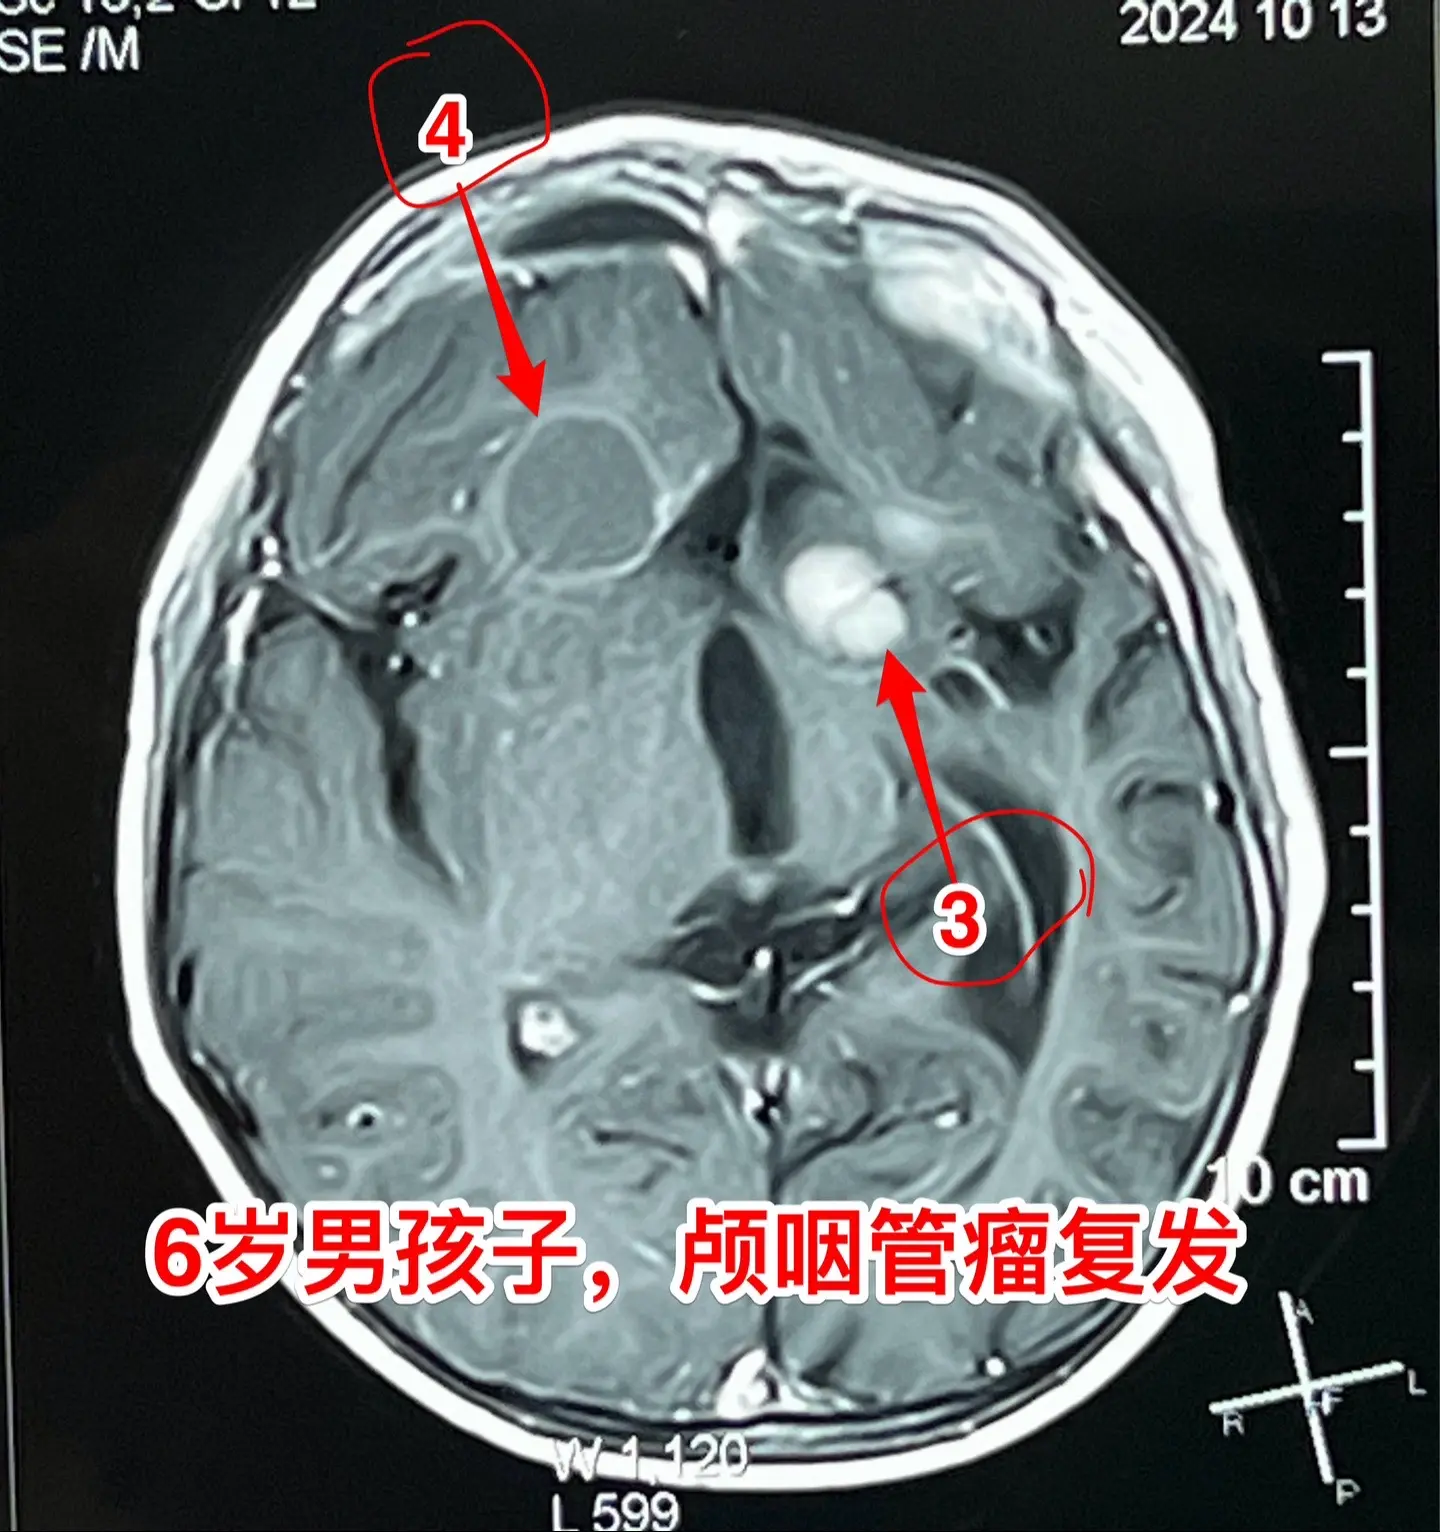

今日两个颅咽管瘤手术。1,6岁男孩子,安徽宿州人。2023年5月因视力下降发现了脑部长了巨大颅咽管瘤,见图1。家长曾经通过微信找我看过,最终选择在上海某医院行手术治疗,手术后出现右侧偏瘫,经过康复治疗后能勉强走路,但是右手还不能拿笔写字。2023.12磁共振就显示颅咽管瘤复发了(多块肿瘤复发)。2024.10又出现视力下降,故来找我作手术。今天手术中发现有四块较大的肿瘤,同时有很多个小钙化。所见肿瘤均顺利切除了。对比两次手术前的磁共振,可以说第一次手术更容易达到完全切除肿瘤,很遗憾,那一次机会错过了。 2,9岁男孩子,江苏盐城市的。因头痛、呕吐检查发现脑部有典型的颅咽管瘤,伴有脑积水。病人到我科住院后经用甘露醇和地塞米松后头痛、呕吐症状消失,能正常吃喝。今日作了开颅手术,顺利切除肿瘤。